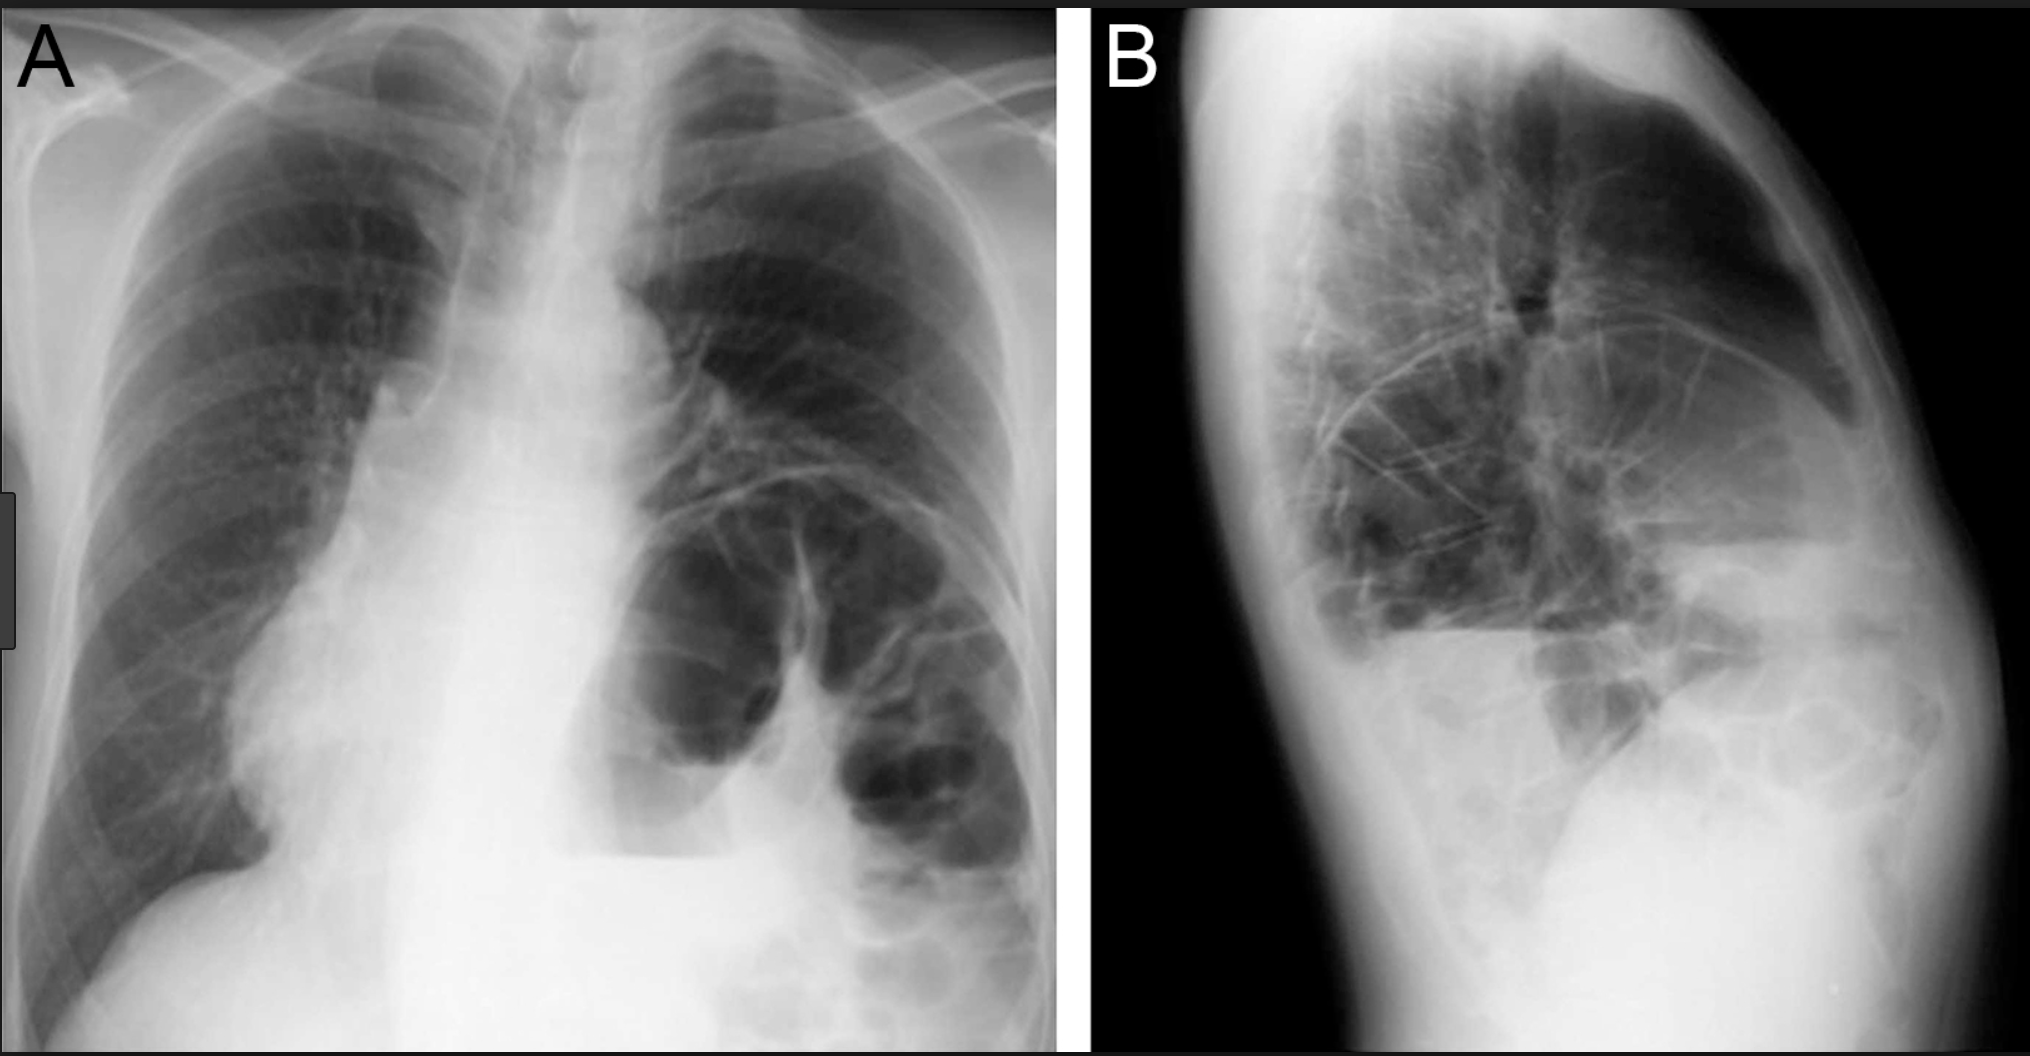

Pneumonia

But where?